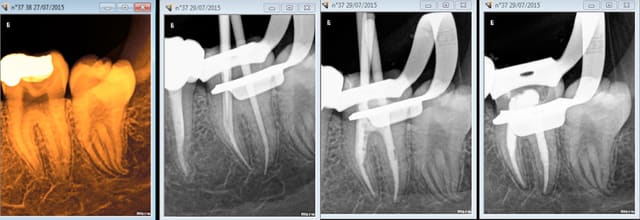

1 .Essayage cones en place, couper ce qui dépasse le cas échéant ( une sur instrumentation ca arrive)

2. scellement des cones.

3. couper les cones au friendo puis phase de descente au friendo ( qui est un heater plugger je le rappelle) et compactage au machtou.

4. coincer les chutes de gutta à l' entrée des canaux et les thermo-compacter au mac spadden.

C'est pret ! -))))